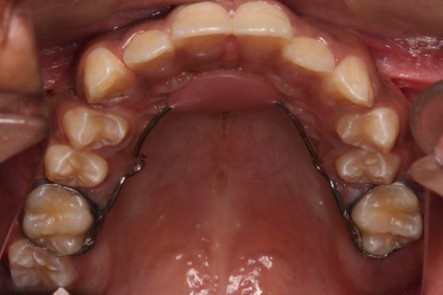

- Pulpotomy, pulpectomy

- Interceptive or habit breaking orthodontics to minimize teeth and jaw irregularities.